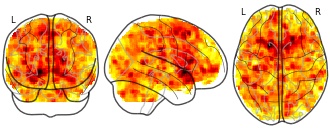

Behavioural and neural characterization of optimistic reinforcement...

License information was derived automaticallyDescriptiondifference between optimist (greater learning rate for positive prediction errors) and unbiased concerning Reward prediction error representation

Collection description

Subject species

homo sapiens

Modality

fMRI-BOLD

Analysis level

group

Cognitive paradigm (task)

instrumental learning task

Map type

T